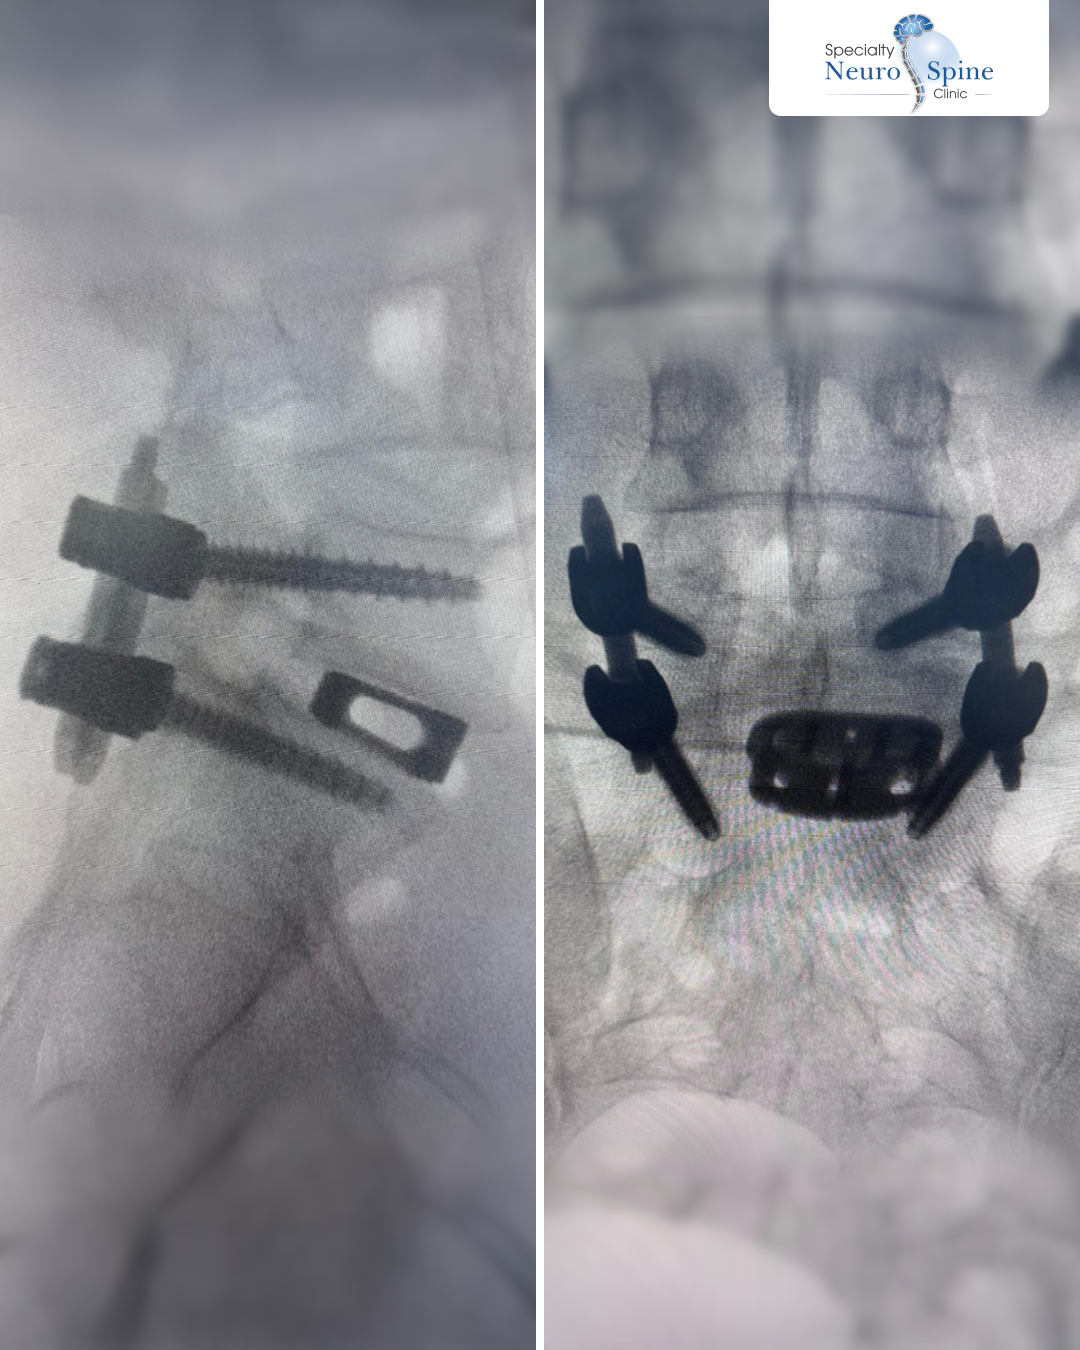

زارتنا مريضتنا الغالية داليا، من العراق، البالغة من العمر 26 عاماً، خضعت لعملية إزالة الانزلاق الغضروفي وتثبيت الفقرات باستخدام التدخلات الجراحية المحدودة.

Oblique Lumbar Interbody Fusion

(OLIF)

أول من اجرى هذه العملية في الشرق الأوسط وآسيا وأفريقيا، الدكتور فراس الحسبـان.